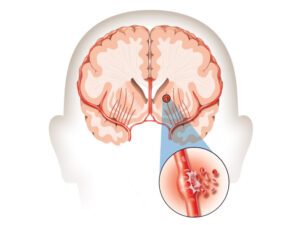

(2) Đột quỵ xuất huyết não (hemorrhagic stroke):

Ít phổ biến hơn nhưng lại nghiêm trọng hơn, xảy ra khi một mạch máu trong não bị vỡ, gây ra xuất huyết vào bên trong hoặc xung quanh mô não.